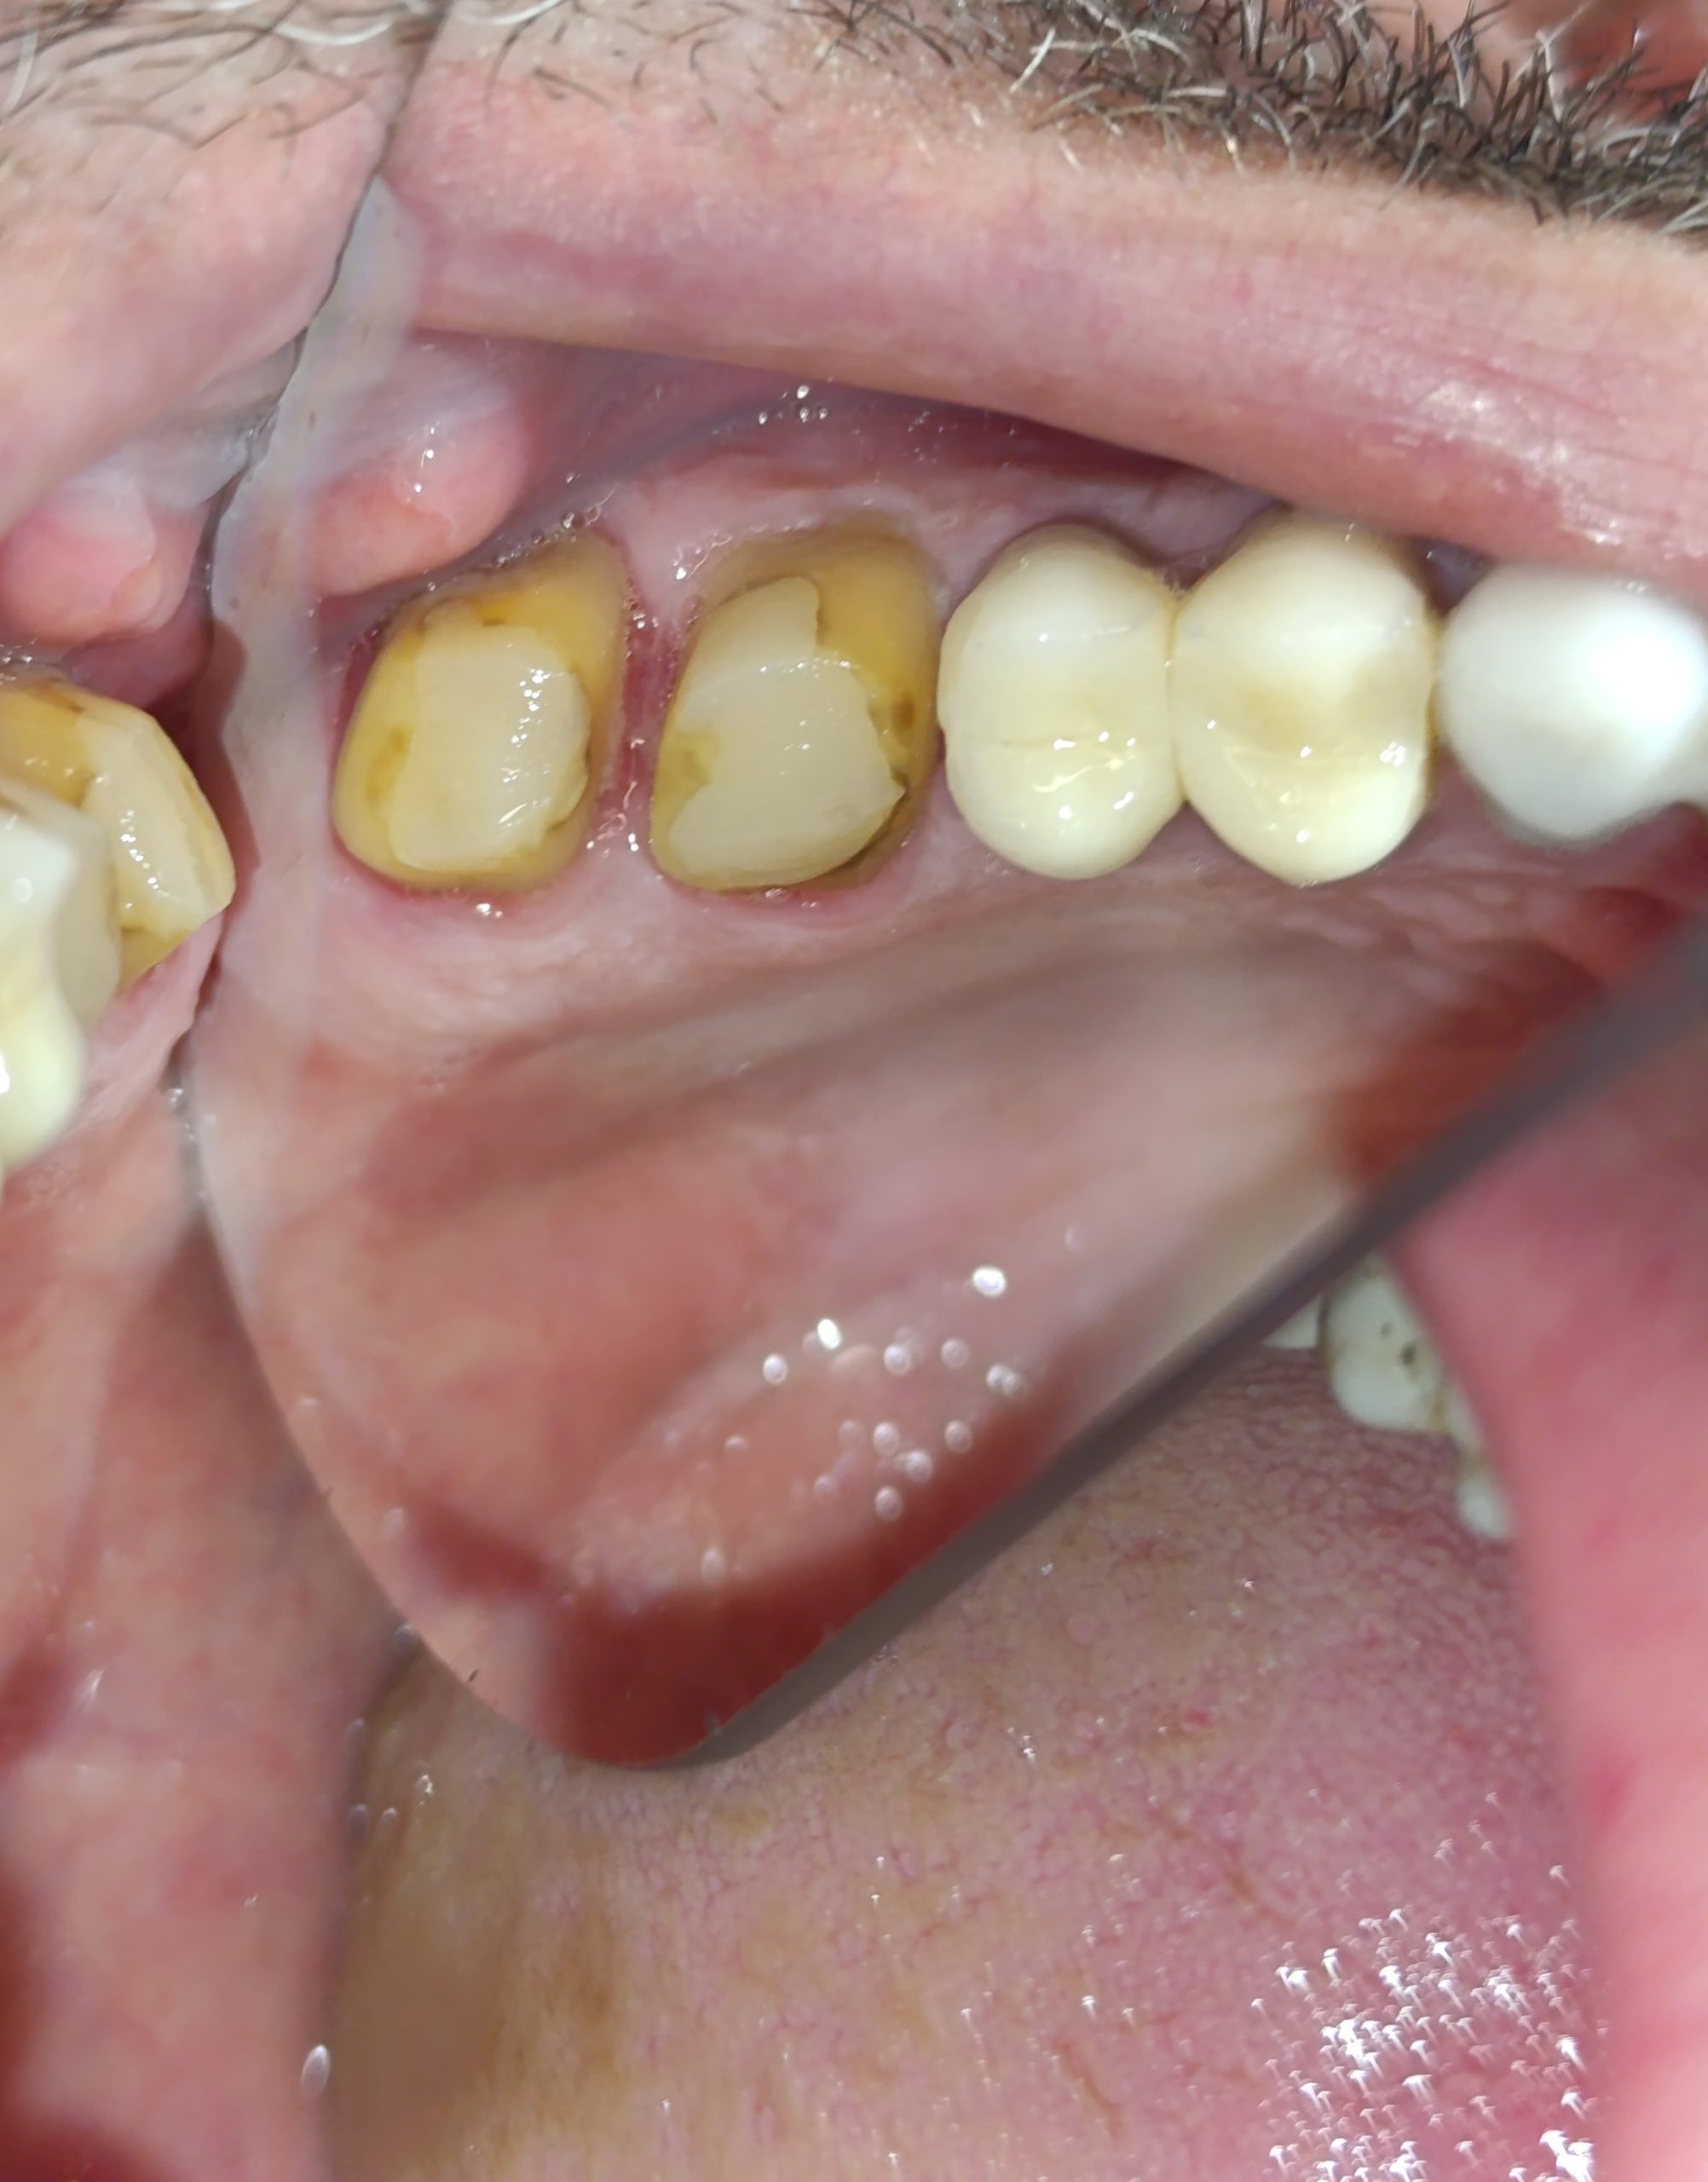

Περιστατικό – Ολοκεραμικές θήκες ζιρκονίου στην αριστερή πλευρά της άνω γνάθου

Ο ασθενής είχε δύο παλιές μεταλλοκεραμικές θήκες, οι οποίες με την πάροδο του χρόνου τερηδονίστηκαν, φθάρθηκαν (είχε φθαρεί η κεραμική κάλυψη των θηκών) και έπρεπε να αντικατασταθούν με νέες (απουσιάζει η φωτογραφία της αρχικής εικόνας). Εφόσον αφαιρέθηκαν οι παλιές θήκες πραγματοποιήθηκαν όλες οι απαραίτητες οδοντιατρικές εργασίες (απονεύρωσεις δοντιών, ανασύστασεις / σφραγίσματα δοντιών) όπου ήταν απαραίτητο, προκειμένου να κατασκευαστούν νέες ολοκεραμικές θήκες ζιρκονίου.

Στο μεσοδιάστημα που μεσολάβησε ώστε ο οδοντοτεχνίτης να κατασκευάσει τις νέες θήκες δοντιών, τα τροχισμένα δόντια ήταν προστατευμένα με προσωρινές στεφάνες.

Η νέα γέφυρα είχε ένα πολύ καλό αισθητικό και λειτουργικό αποτέλεσμα.

Αρχική εικόνα των δοντιών μετά την αφαίρεση της παλιάς γέφυρας

Τα δόντια μετά τις απαραίτητες απονευρώσεις και τις ανασυστάσεις

ΤΕΛΙΚΗ ΕΙΚΟΝΑ